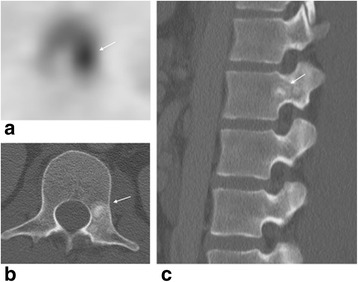

Low back pain in young athletes not related to sports activity

Since bone scintigraphy has limited specificity, correlation with additional imaging, particularly with CT is necessary to further clarify the bony abnormality. Differential diagnosis for uptake in a vertebra in this age group includes infection, benign lesions like osteoid osteoma, osteoblastoma, aneurysmal bone cyst, and chondroblastoma, and rare malignant lesions like osteosarcoma. Osteoid osteoma and osteoblastoma often involve the posterior spinal elements, with the thoracolumbar spine being the most common site of involvement. Osteoid osteoma affects the spine in 10–20 % of cases [28] and is presenting as a sclerotic lesion with a radiolucent nidus (Fig. 6). Patients have back pain, spinal deformity, and nerve root compression symptoms. The most common location is in the posterior elements lamina, facets, pedicle, pars interarticularis, and spinous process. Osteoid osteoma on bone scan appears as a focus of increased radiotracer uptake occasionally with a surrounding area of less intense uptake (“double intensity sign”) [29]. Chondroblastoma is a benign but aggressive neoplasm that may also occur in the vertebral column (vertebral bodies and posterior elements). Osteoblastoma and chondroblastoma occasionally may be associated with an aneurysmal bone cyst.

Fig. 6.

Osteoid osteoma lesion at L1 pedicle with “double intensity sign” on bone scan. a Axial SPECT image show focal increased uptake in the left pedicle with a surrounding area of less intense uptake (“double intensity sign“). b Axial CT image of L1 vertebra and c sagittal image of the spine (between T12 and L3 levels) show a sclerotic lesion at L1 left pedicle with a central lucency which is almost completely calcified